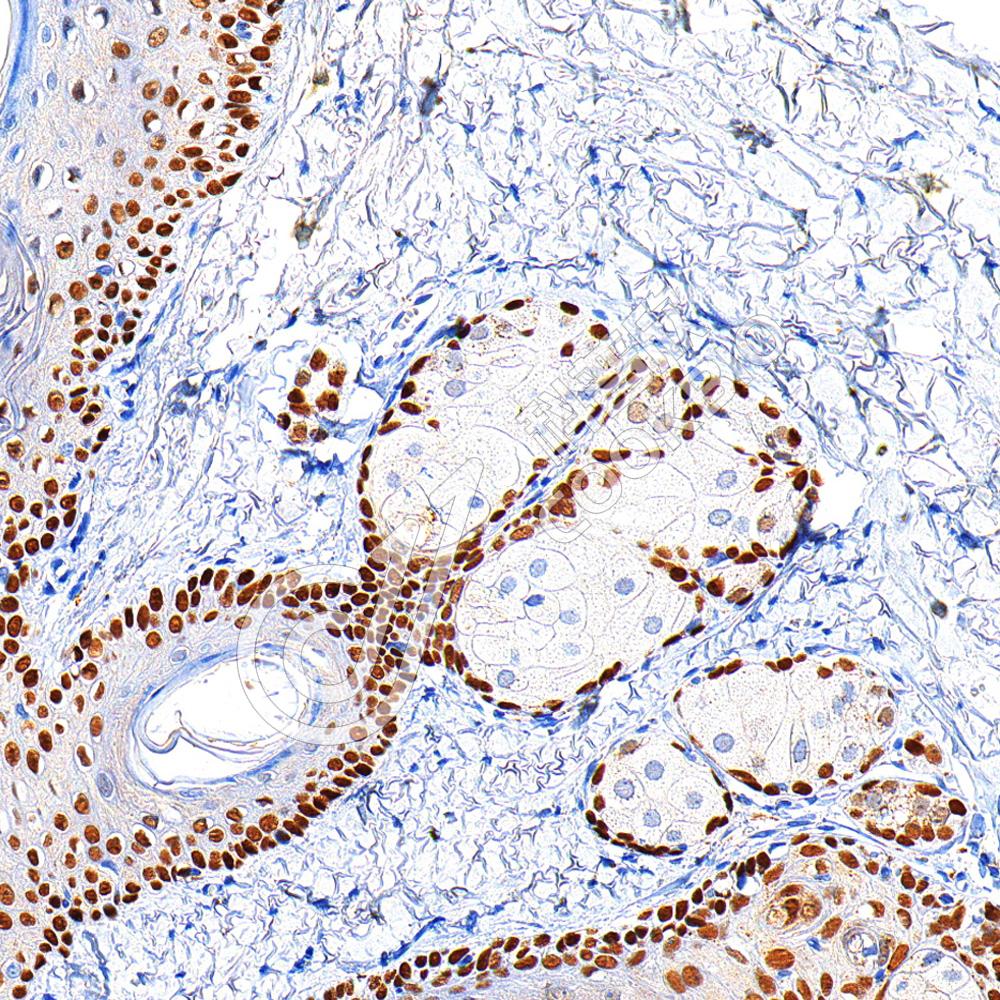

IHC检测p63蛋白(货号 K5450036).

样品: 人宫颈癌, 4%多聚甲醛 (货号KSG1101) 固定12-24小时.

抗原修复: 柠檬酸抗原修复液(干粉, pH 6.0) (KSG1201), 高压锅均匀喷气计时2分钟.

—抗: 1: 600稀释, 4℃ 孵育过夜.

二抗: S-vision免疫组化多聚二抗(山羊抗小鼠), 即用型(货号KB3903), 室温孵育20分钟.